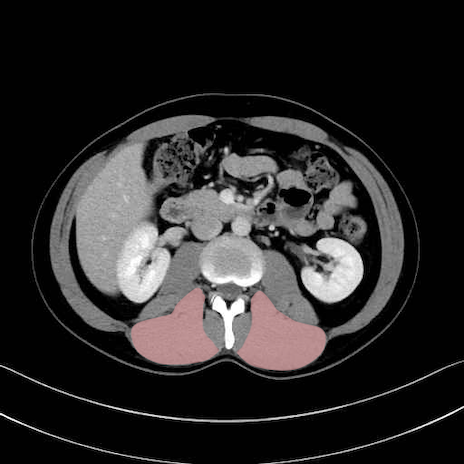

脊柱起立筋 (Erector spinae)

多裂筋 (Multifidus)